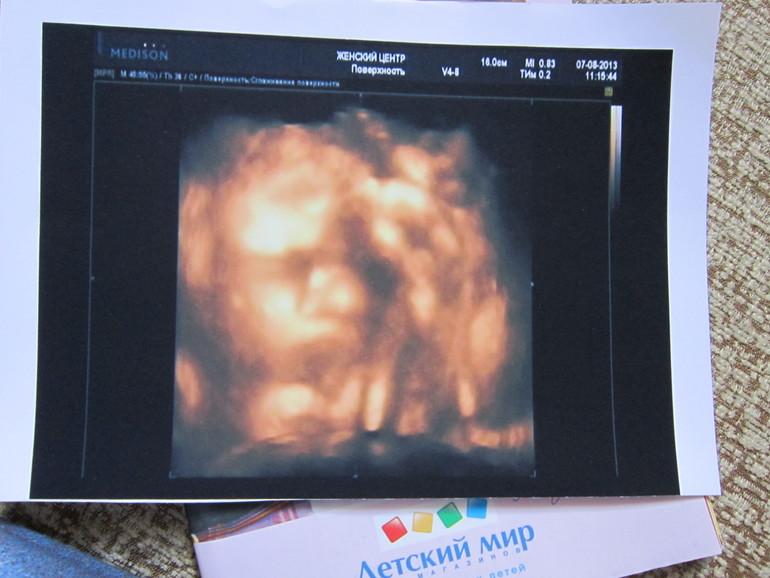

Моя хулиганка сидит на попе и не дергается) Чем собственно меня немного огорчила. Зато по развитию убежала вперед на 3 дня и по узи срок родов получился раньше)) Вес 1530. Сердечко бьется 135 ударов в минуту) Показали личико дочки, но вот она отказалась совсем показываться) Она практически в самом начале взяла и закрыла кулачками личико) Одни глазки были видны) Обвития нет сейчас, пуповина лежит на груди дочки как бусы.

Но я так рада видеть мою крошку) Хоть и плохо видно, но глаз, нос и ротик разлечить можно))